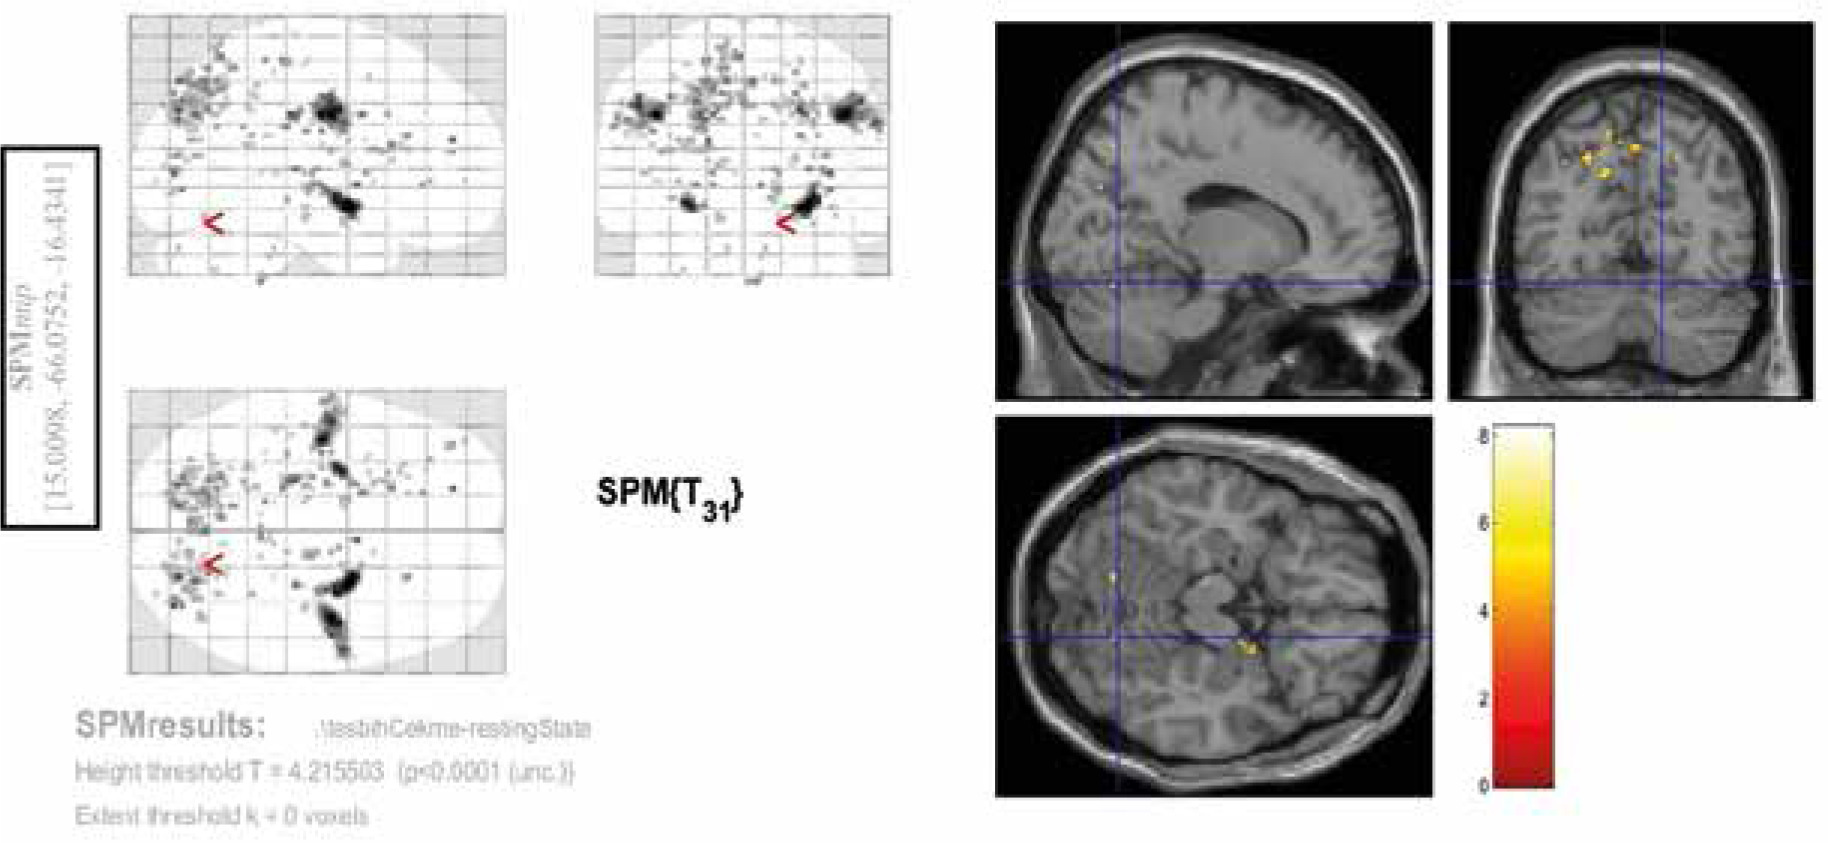

Figure 2

Activated areas in second-level analysis during the spontaneous chewing task. The coordinates of these regions are provided in the blue rectangle on the left